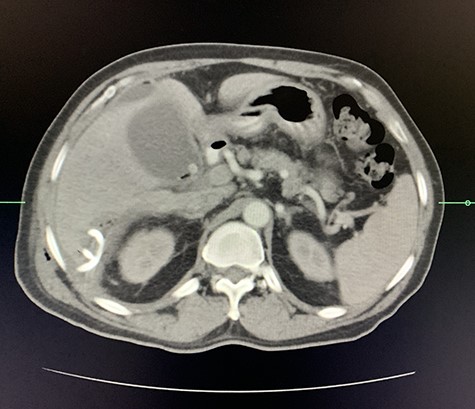

A computed tomography (CT) scan of the abdomen revealed an enlarged, thickened gallbladder with multiple stones, communicating with an intrahepatic collection in segment 4 measuring 116 × 80 mm, with an associated air fluid level and air locules (Fig. 1). There was an apparent fistulous tract to the hepatic flexure of the colon, another large collection in segment 6 (97 × 96 mm) as well as other smaller collections (Figs 2 and 3).

Axial view of CT scan of the abdomen with oral contrast demonstrating enlarged, thickened gallbladder with radio-opaque gallstones. Two large liver abscesses in segment 4 measuring 116 × 80 mm (communicating with the gallbladder) and segment 6 measuring 97 × 96 mm with air locules noted.